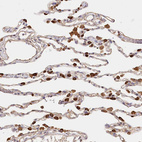

Immunohistochemical staining of human liver shows strong cytoplasmic positivity in hepatocytes.